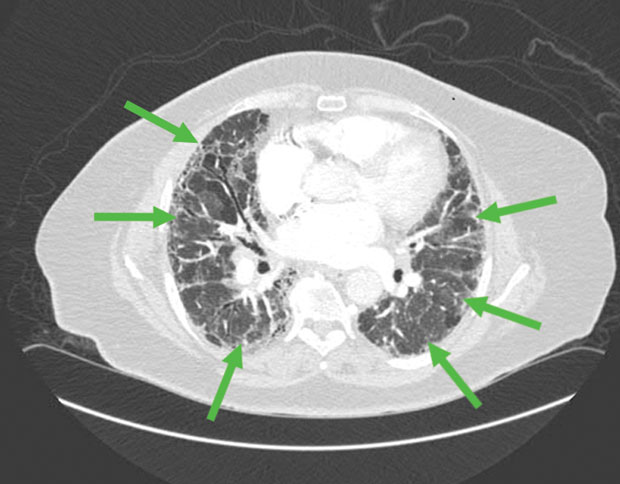

High-resolution CT scan of the chest reveals bilateral subpleural and basilar reticular changes consistent with idiopathic pulmonary fibrosis.

The most appropriate next step in management of this patient with newly diagnosed idiopathic pulmonary fibrosis (IPF) is to start nintedanib (Option A). IPF is a progressive and ultimately fatal fibrotic lung disease with a median survival of 3 to 5 years. Diagnosis rests on the exclusion of other causes of diffuse parenchymal lung disease and demonstration of characteristic radiographic changes of bilateral, subpleural, and basilar reticular changes. Subpleural basilar reticular and ground-glass opacities (shown by arrows in the image) are characteristic of IPF. Management of IPF should include consideration of antifibrotic therapies and oxygen supplementation for hypoxemia. Nintedanib, a tyrosine kinase inhibitor, and pirfenidone, an antifibrotic agent, are first-line medical therapies in IPF. Both medications decrease disease progression, but neither is curative. The clinical course of IPF is unpredictable, and patients can experience acute exacerbations with accelerated decline. Referral to a specialist in IPF is advisable upon diagnosis, and early consideration should be given to referral to a lung transplantation center. This patient has a clinical and radiographic presentation consistent with IPF and should begin receiving antifibrotic therapy with nintedanib or pirfenidone.